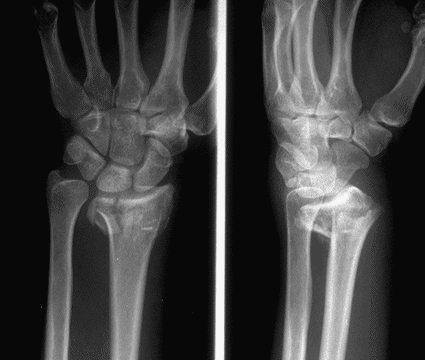

Case 2 Preop